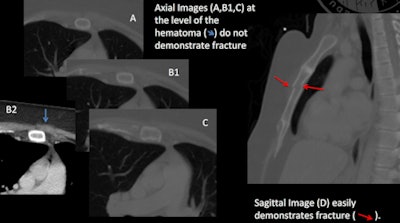

Sternal injuries may be obscured on axial imaging due to the curved configuration of the anterior chest wall. That's a real problem because sternal injury is not only a direct source of pain, it can also indicate the presence of aortic or cardiac injury, according to the team.

Five readers independently assessed deidentified sets of axial-only trauma chest CT images, and then, at a later date, a deidentified set of sagittal-only images of the same trauma chest CT. The radiologists recorded findings for the presence of a sternal injury (including secondary signs of sternal injuries such as adjacent hematomas), and assessed their confidence for the presence or absence of a sternal injury on a five-point scale.